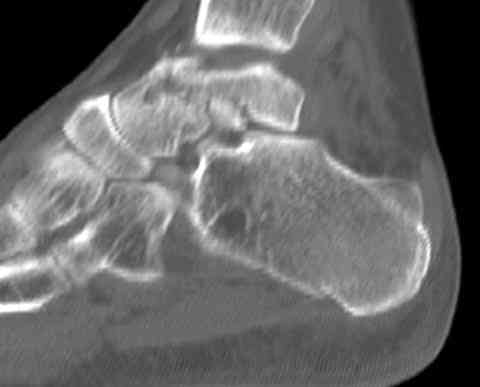

И второй случай из недавней ташкентской практики, (извините за качество ренгенограммы и только в одной проекции) случай падения с высоты (кстати моего друга - известного киноактера) - открытый

смещенный перелом тарана, с переломом переднего края дистального эпиметафиза большеберцовой кости.

При поступлении в приемной сделана первичная обработка с ушиванием открытой латеральной раны и вытяжением за пятку.

Из-за отсутствия времени пришлось оперировать на второе утро, из материала, что имеем на месте, фиксирован двумя шурупами, а третий-это контур сломанного жойстика в 4 мм. На дистальный медиальный конец тибиа antiglide 3.5 мм пластина. Через пару дней выписан и несмотря на предупреждение, самостоятельно начал нагрузку в 4 недели, время не ждет, снимается в боевике в Росийской Федерации.